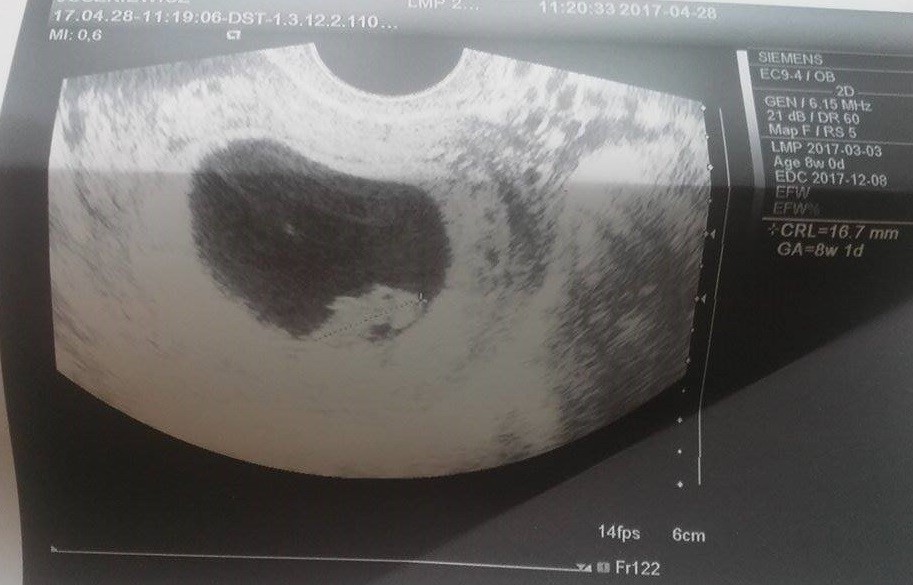

A to jest nasz Dziedzic :)

Hej, była obsuwa, właśnie skończyłam wizytę. Chyba zaraz latać zacznę :) Maleństwo sporo urosło i jak wcześniej było o 3 dni młodsze niż wg OM, to teraz o 1 dzień starsze, czyli 8t1d ;) Widziałam i słyszałam serduszko, yupii. Tylko lekarz mi nie dał zdjęć :( ale za to pozwolił cyknąć fotkę jak bardzo poprosiłam. Teraz termin mi się przesunął na 8.12 ciekawe jak to ostatecznie będzie... Sorki że tak chaotycznie ale cała w skowronkach jestem, kolejna wizyta 17.05, a do tego czasu reszta badań.

Zobacz załącznik 804346 Zobacz załącznik 804347 Zobacz załącznik 804348